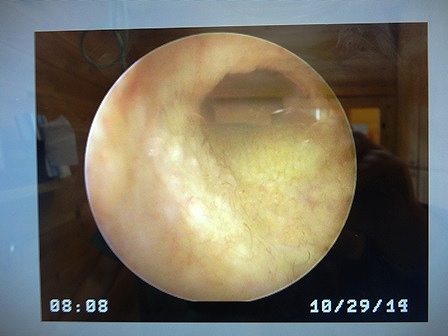

終わってから、画像を見せてもらって

これは今日のもの

昨日より、綺麗になっているよって

洗浄液を耳に入れて、スポイトで吸い取ると

昨日は、濁っていた水が、今日はそれほど汚れていなかったらしい

このまま、洗浄続ければ、綺麗になるかなぁ~~

早く、鼓膜が見えるようになりますように![]()